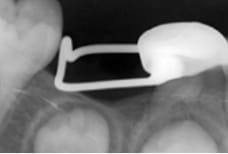

バンドループ / クラウンループ

永久歯が生えてくるまで、ワイヤーを使って永久歯の場所が狭くならないようにします。

(左:バンドループ / 右:クラウンループ)(上:バンドループ / 下:クラウンループ)